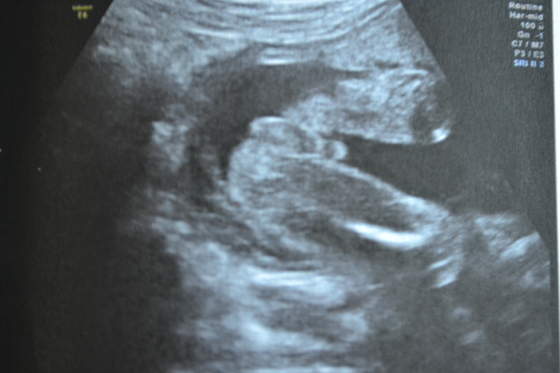

A tu nasz Adrianek: